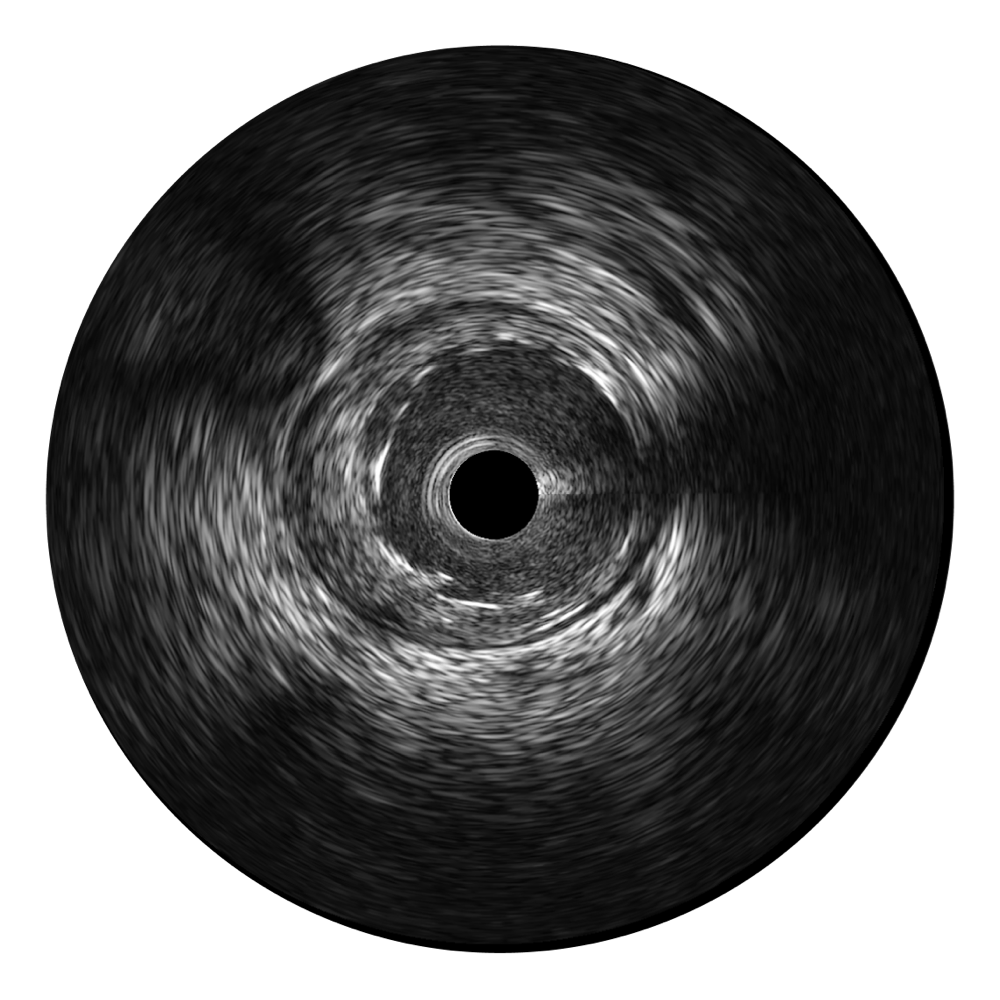

1xBET宽频IVUS图像

对比传统IVUS导管成像,1xBET宽频IVUS图像的近场支架梁显影更细腻,远场中膜外血管仍清晰可辨,兼顾远中近,兼顾分辨力与穿透深度